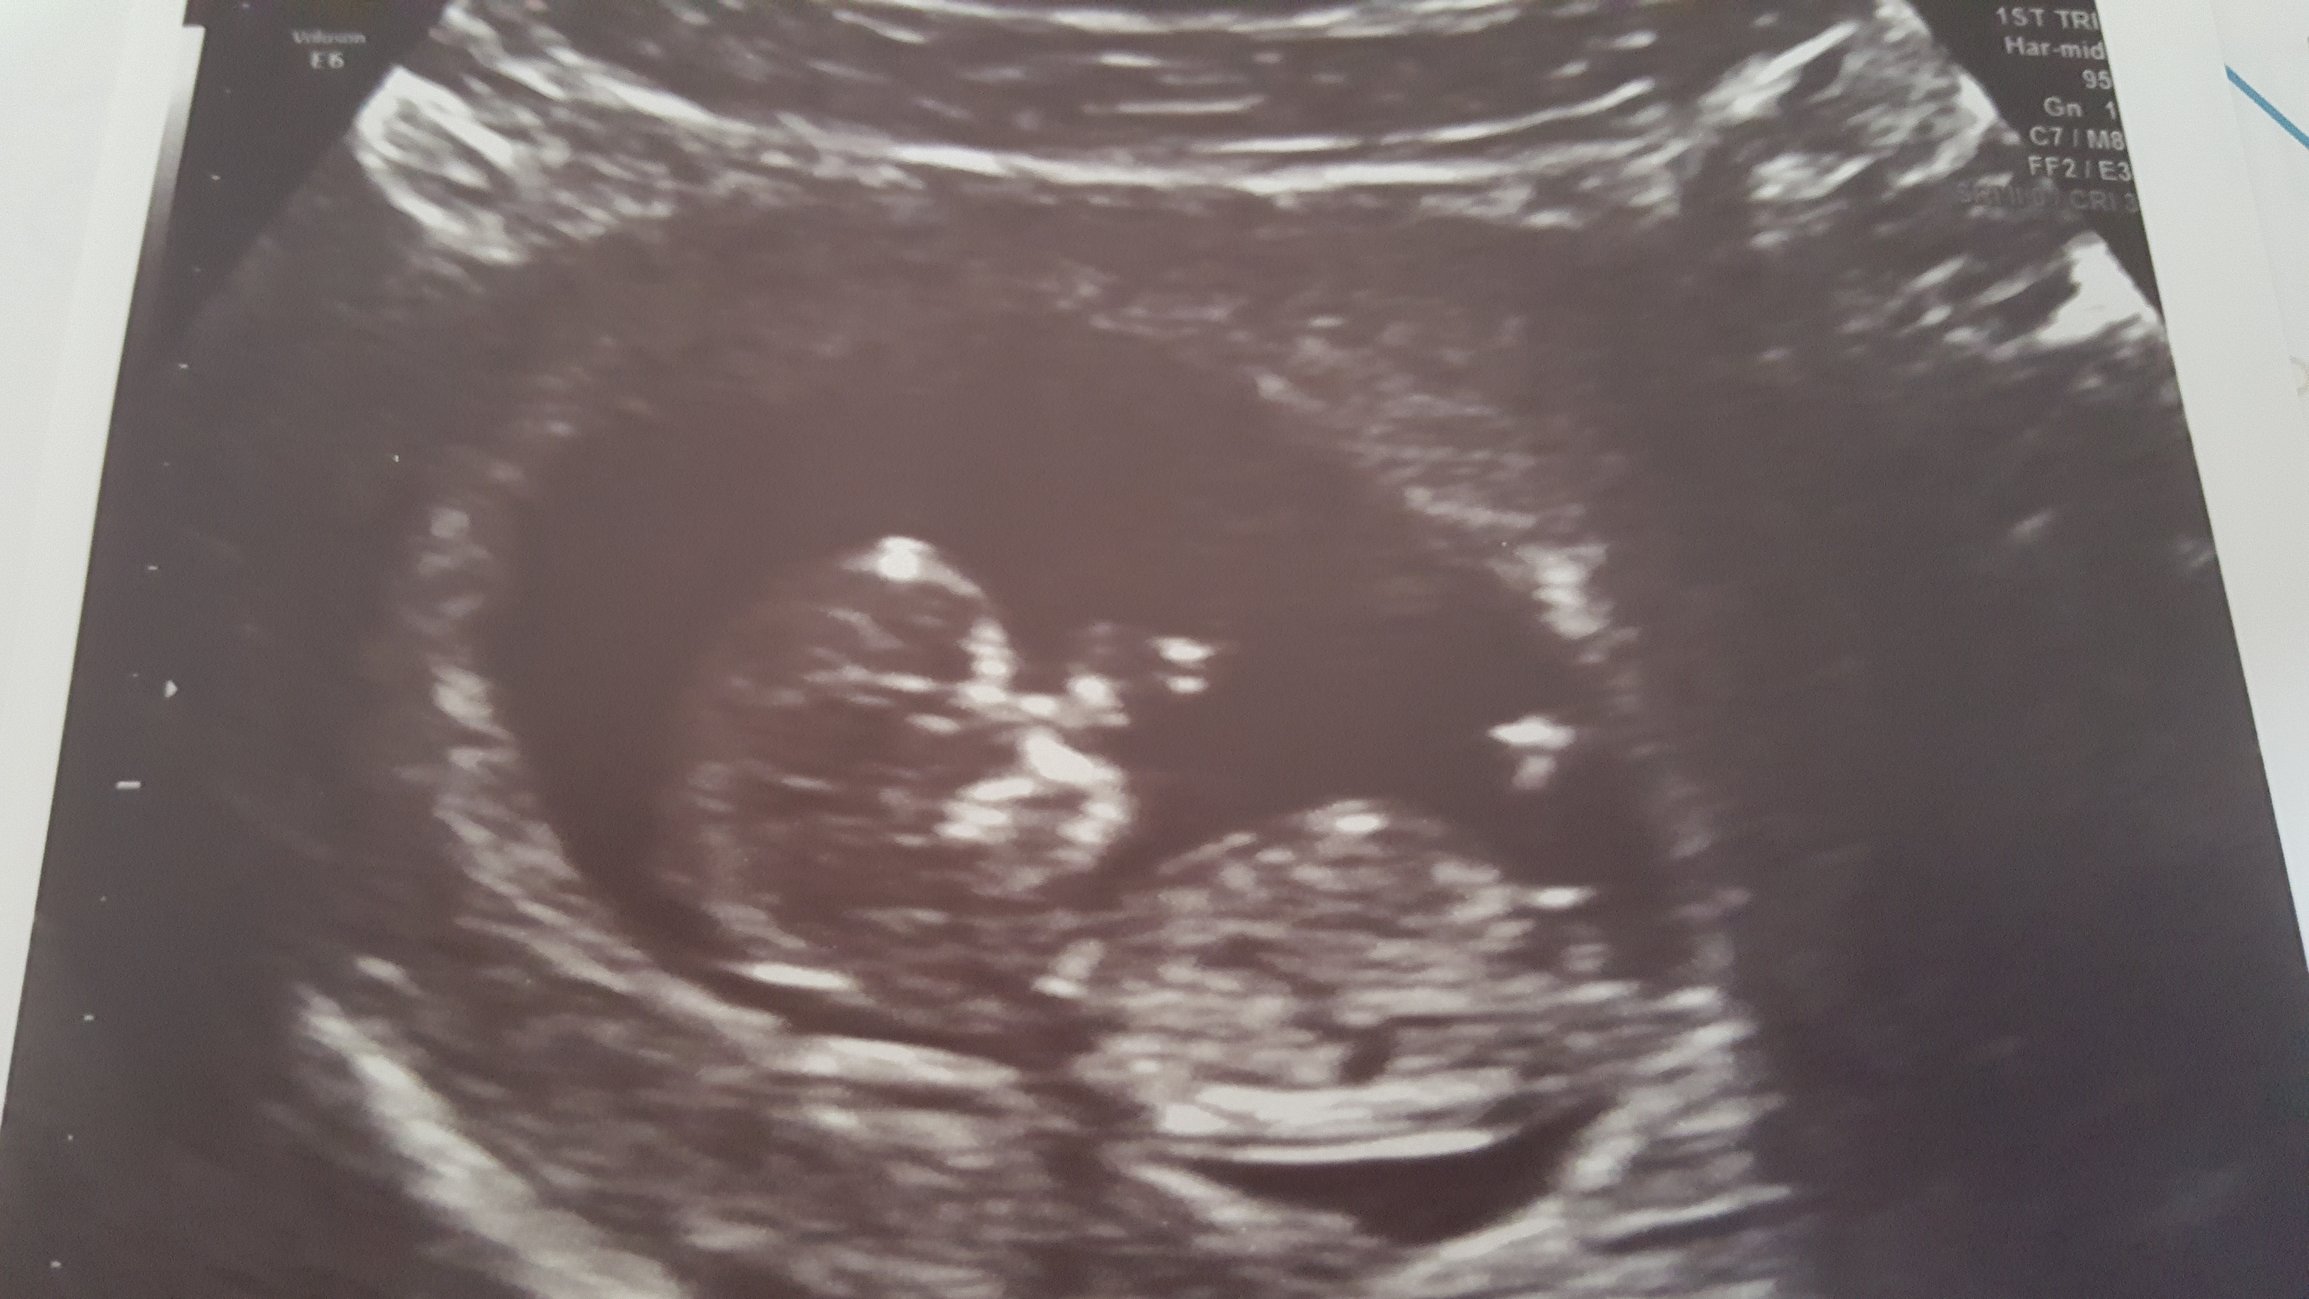

We got to see our wee one again! Looking good and healthy, and this one got to be an external u/s. He even turned to look right at us and waved! Heart is full and happy.

@dragonfaerie Ahhhh! It looks like a baby!!! I can't wait until my little one doesn't look like a blob anymore. Congrats on your good news yesterday (and not having to have an internal US anymore!).

@dragonfaerie gosh, how cute is that? I love it. Love that you go an external u/s already...what a sweet moment.

@dragonfaerie - Great pic! you say "he" so does that mean you are having a boy? I must have missed that. Congrats & welcome to team blue